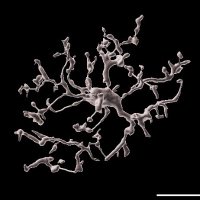

PhD. candidate, neuroscience, microglia

PhD. candidate, neuroscience, microglia